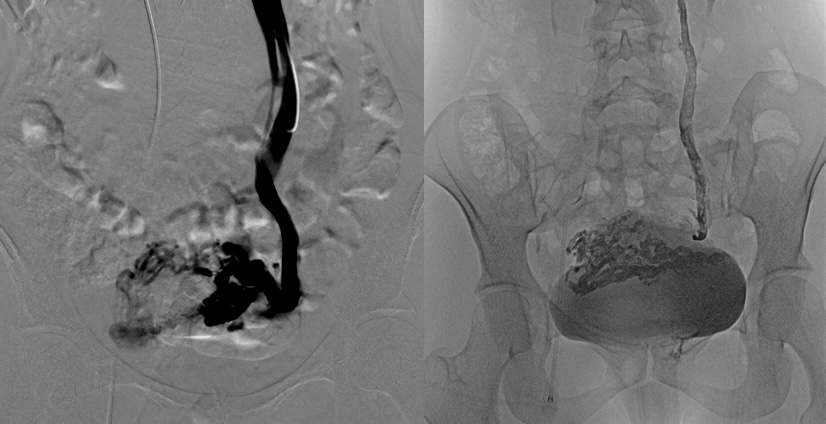

3. Phlébographie : une injection de produit de contraste iodé (comme pour un scanner) est utilisée pour réaliser une cartographie précise.

4. Embolisation : Une fois que le cathéter est placé au bon endroit, le matériel d'embolisation est injecté dans les veines afin de les obstruer et de stopper le flux sanguin (colle biologique ou sclérosant).

Phlébographie de la veine ovarienne gauche – Embolisation à la colle biologique